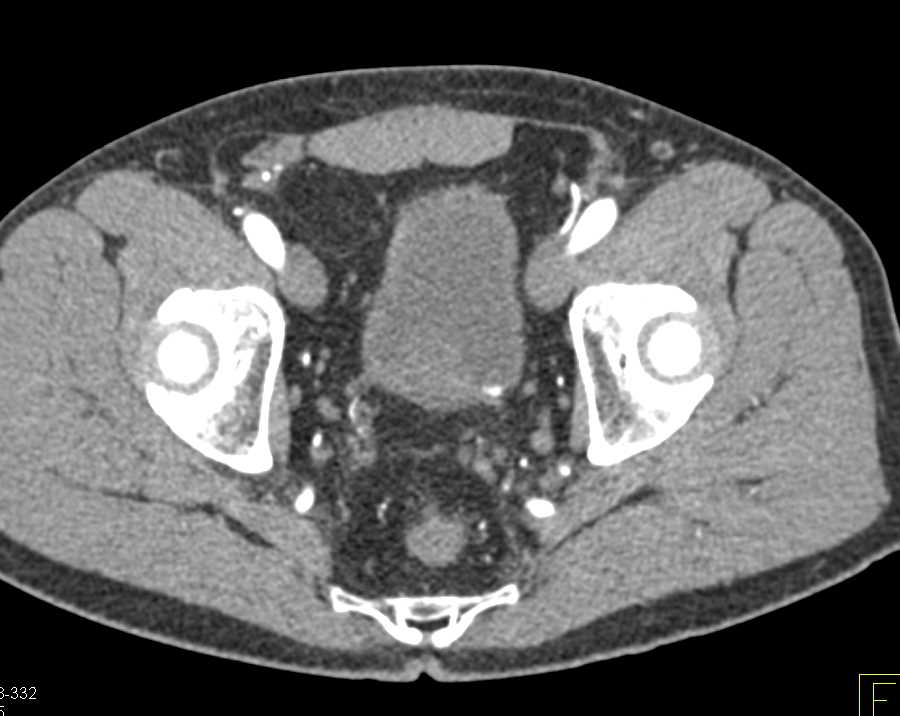

Transitional Cell Carcinoma Left Kidney